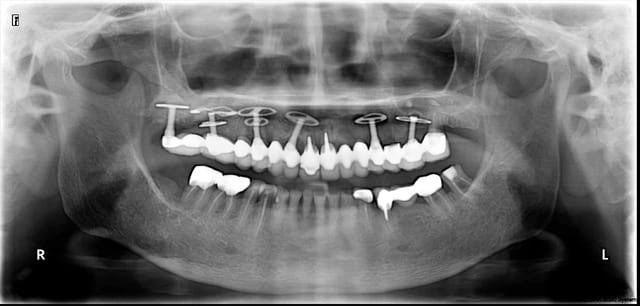

bridges posés avant équilibration occlusale

Mcipe bi maxillaire du 13 f vier 2012 008 sjst7t - Eugenol